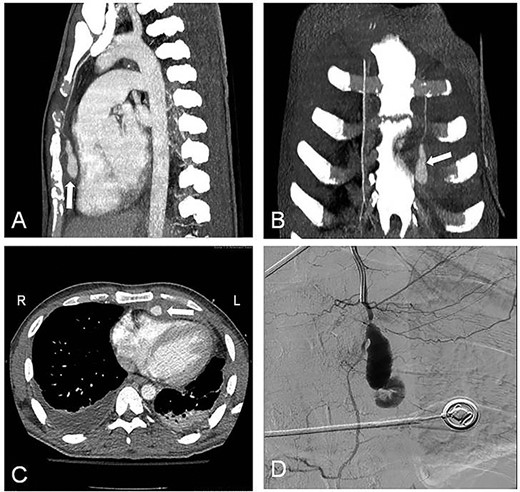

A 22-year-old man was admitted to our emergency department suffering of blunt thoracic trauma due to traffic accident. Clinical examination and performed radiological studies revealed fractures of multiple left-sided ribs, the sternum as well the Th11 and Th12 vertebral bodies. The patient was initially treated conservatively, but on the fifth day, he developed a left-sided pleural effusion, necessitating a thoracostomy tube. Additionally, there were subpectoral chest wall abscesses, which were surgically incised and drained. Blood as well pus cultures from the abscess cavities revealed the growth of Staphylococcus aureus; therefore, intravenous antistaphylococcal antibiotics were administered. However, in the further course, a control contrast-enhanced computed tomography (CT) scan demonstrated a big left IMA pseudoaneurysm (Fig. 1: white arrow) accompanied by an ipsilateral localized hemothorax (Fig. 1A–C). The effusion was drained again, and concerning the aneurysm, we preferred a minimally invasive treatment via coil embolization in order to avoid a potential extensive mobilization of the patient, contraindicated by his spinal injuries, while the positioning on the operating table in case of a surgical treatment through a lateral thoracotomy.

Contrast-enhanced CT with LIMA pseudoaneurysm (white arrow). (A) Sagittal plane; (B) coronal plane; (C) transverse plane with LIMA pseudoaneurysm (white arrow) and bilateral pleural effusions; (D) selective LIMA angiography demonstrating the aneurysm.